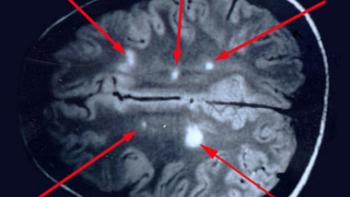

Imagen

La esclerosis múltiple es una enfermedad neurodegenerativa.

La esclerosis múltiple (EM) es una enfermedad neurodegenerativa y crónica del sistema nervioso central. No existe cura y las causas exactas son desconocidas. Puede presentar una serie de síntomas que aparecen en ataques o que progresan lentamente a lo largo del tiempo.